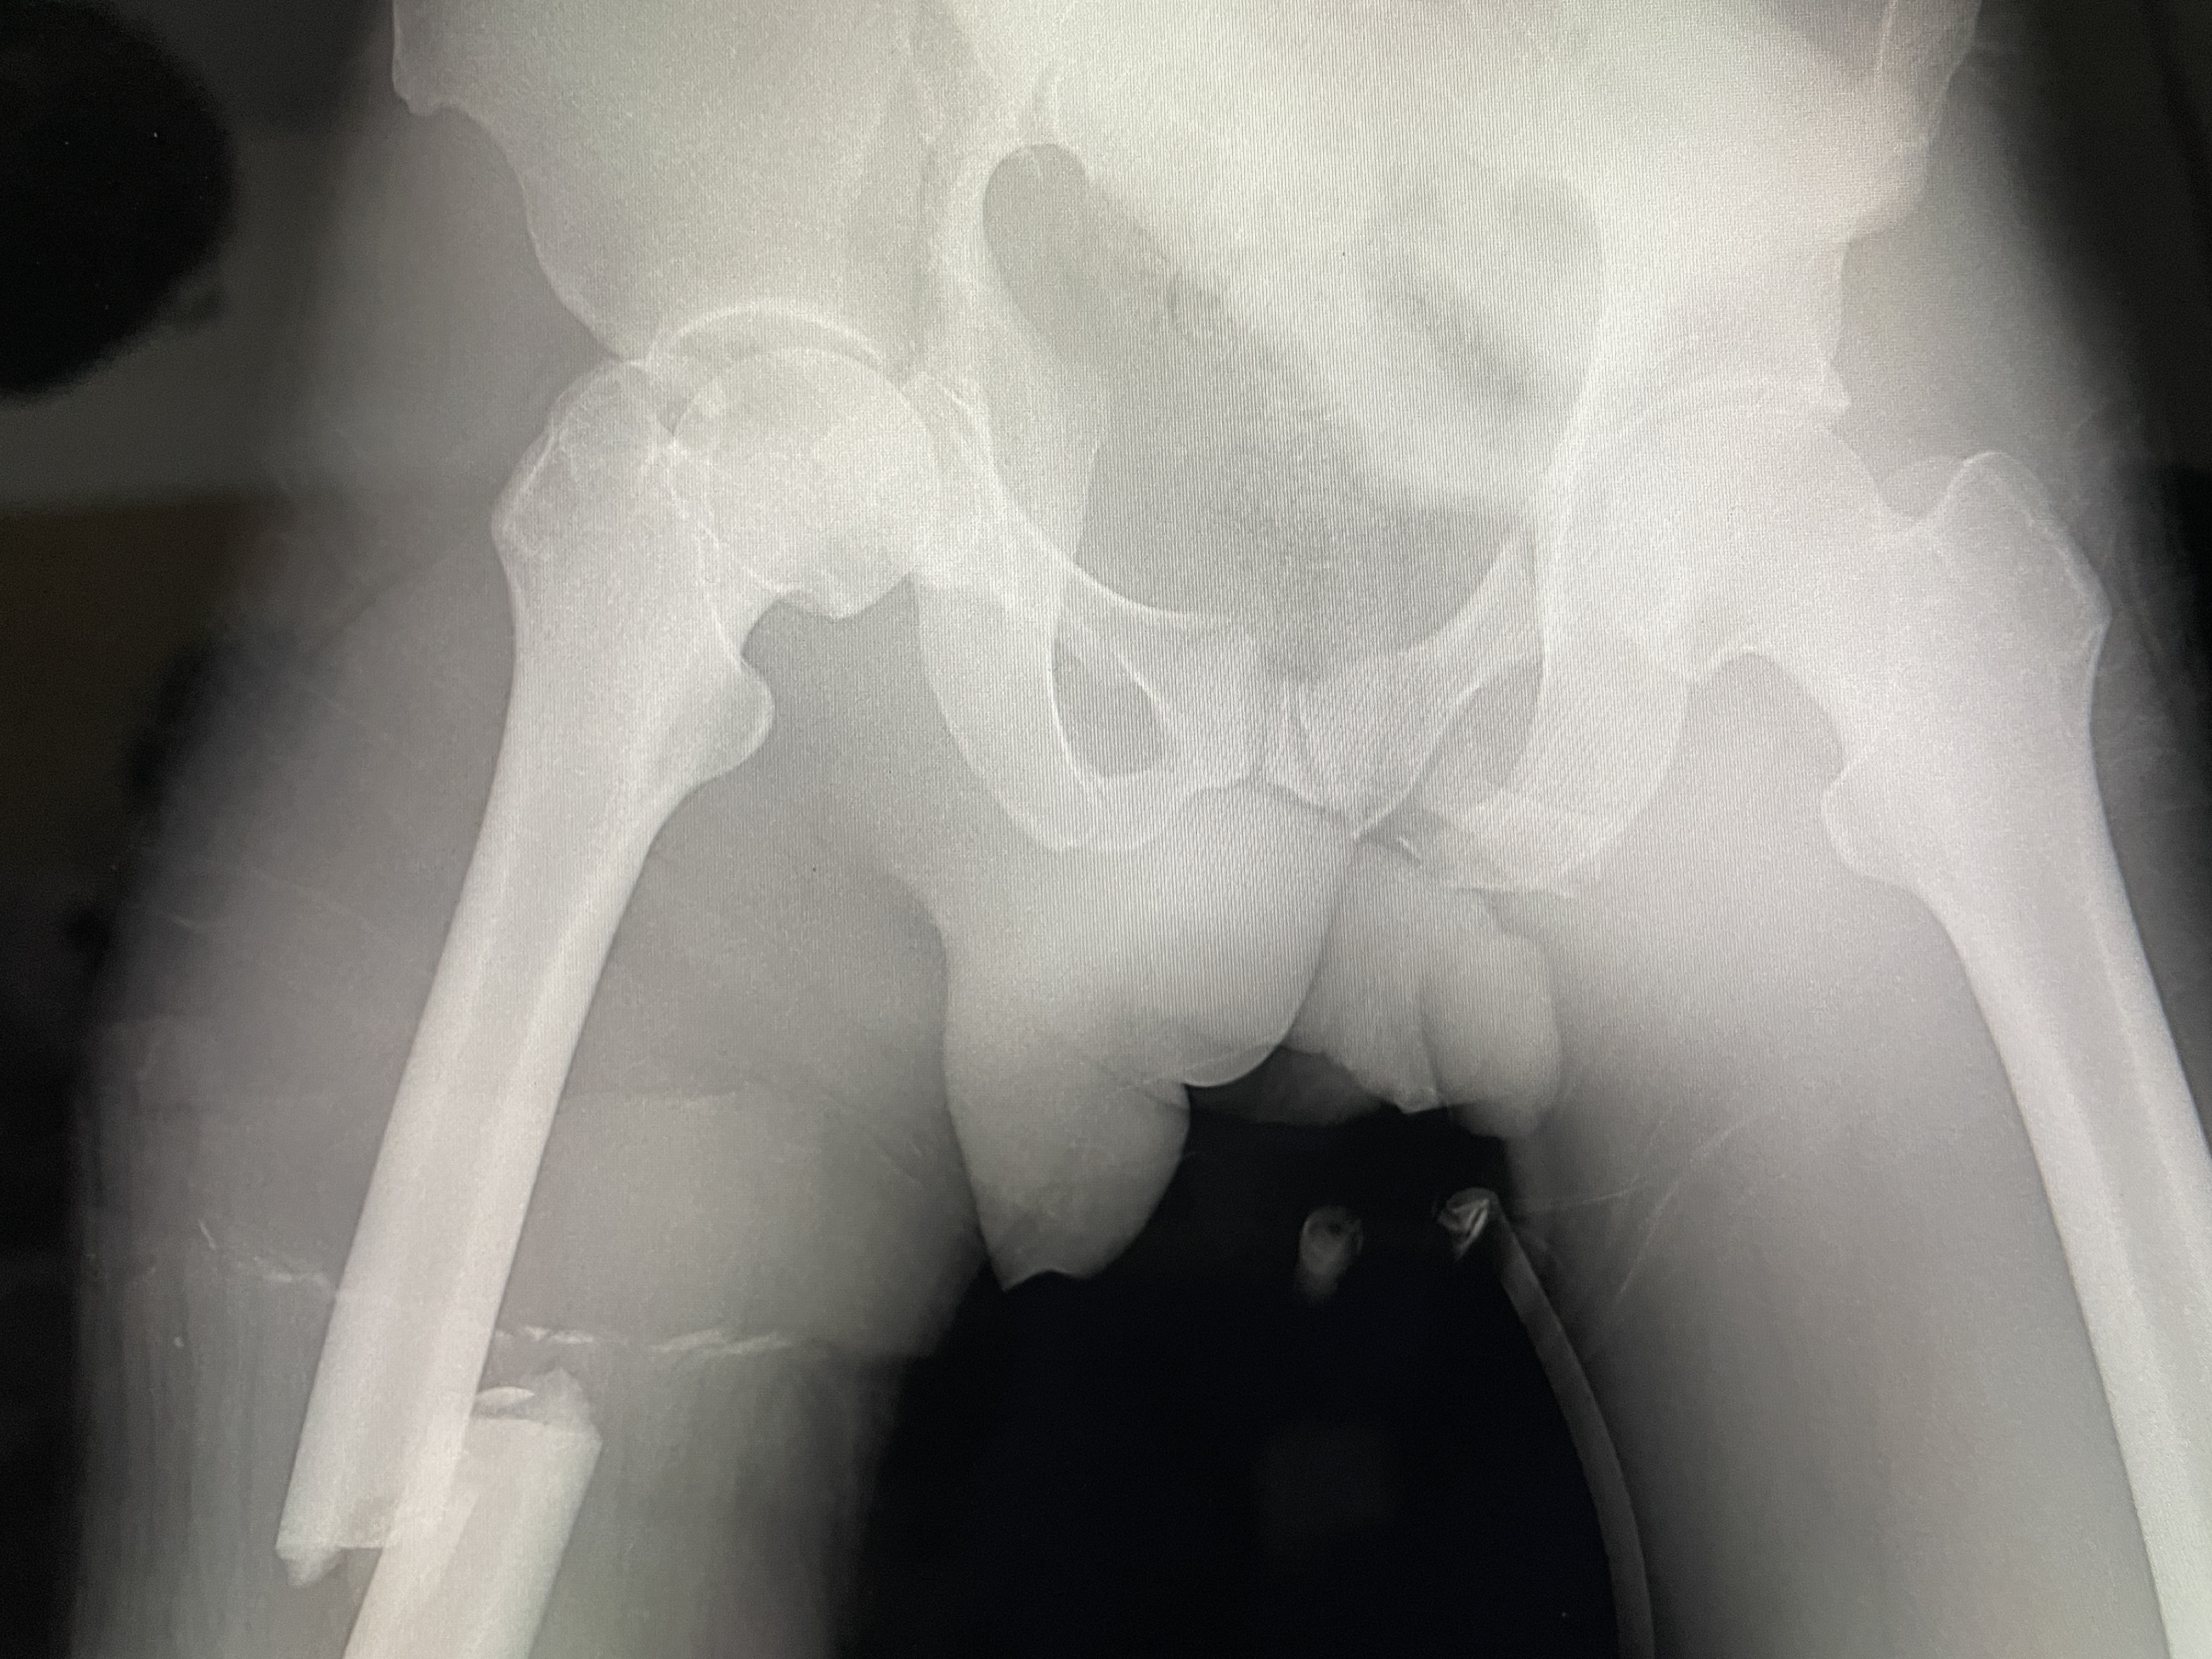

I walk back in to the OR and my next patient who has a pelvic fracture and a broken femur is sitting up because the anesthetist wants to put a spinal in. I’m shocked that he sat up at the anesthetist’s insistence with a broken pelvis. Since he’s already sitting up I tell Phillippe to go ahead with the spinal. This guy was making mud bricks at the edge of a large termite mound. They can get about 7-10 feet tall. As he dug out dirt from it, it fell on him, breaking his femur and pelvis. He came in with the traditional wood splinting. I asked the nurses what the traditional healer would charge to do that and they guessed $40 equivalent. We took off the splint and prepped his lower leg and I put a steinmen pin in the tibia for traction. I’ll send a picture with either this email or the next with him in his bed. It was quite a work of ingenuity, that involved a number of people.